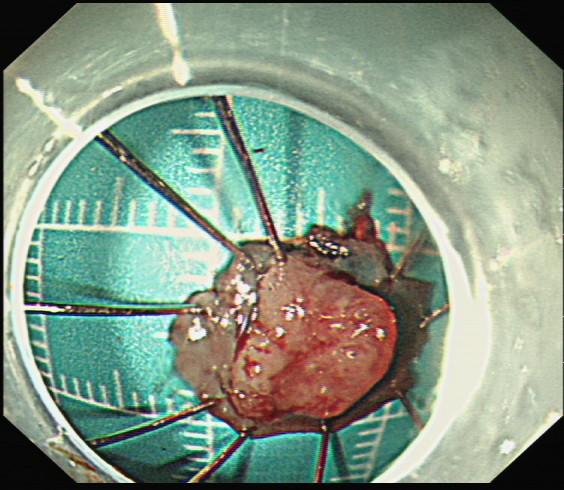

微创“拆弹”:内镜下的精准手术——ESD

在省人民医院专科联盟指导下ESD手术顺利完成,为什么“完整剥离”如此重要? 因为只有这样,才能将病灶连根拔起,并获取完整的病理标本,为后续的诊断和治疗提供最可靠的依据。也避免了外科开腹手术。

黄女士成功接受了ESD手术。术后病理分析证实了术前的判断:绒毛状管状腺瘤,局灶高级别上皮内瘤变。